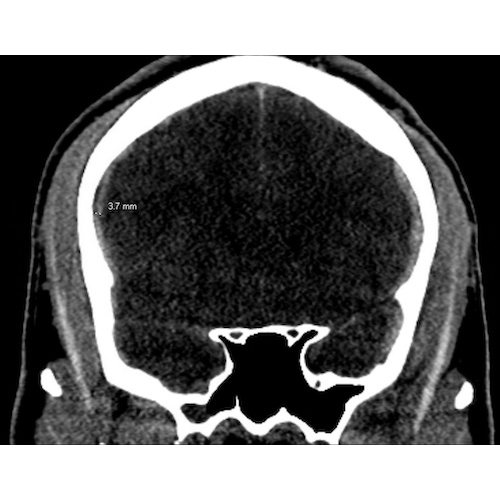

| A Fellow's Role In Multiteam Coordination For Severe Brain Injury Management In Football - Page #3 | |||